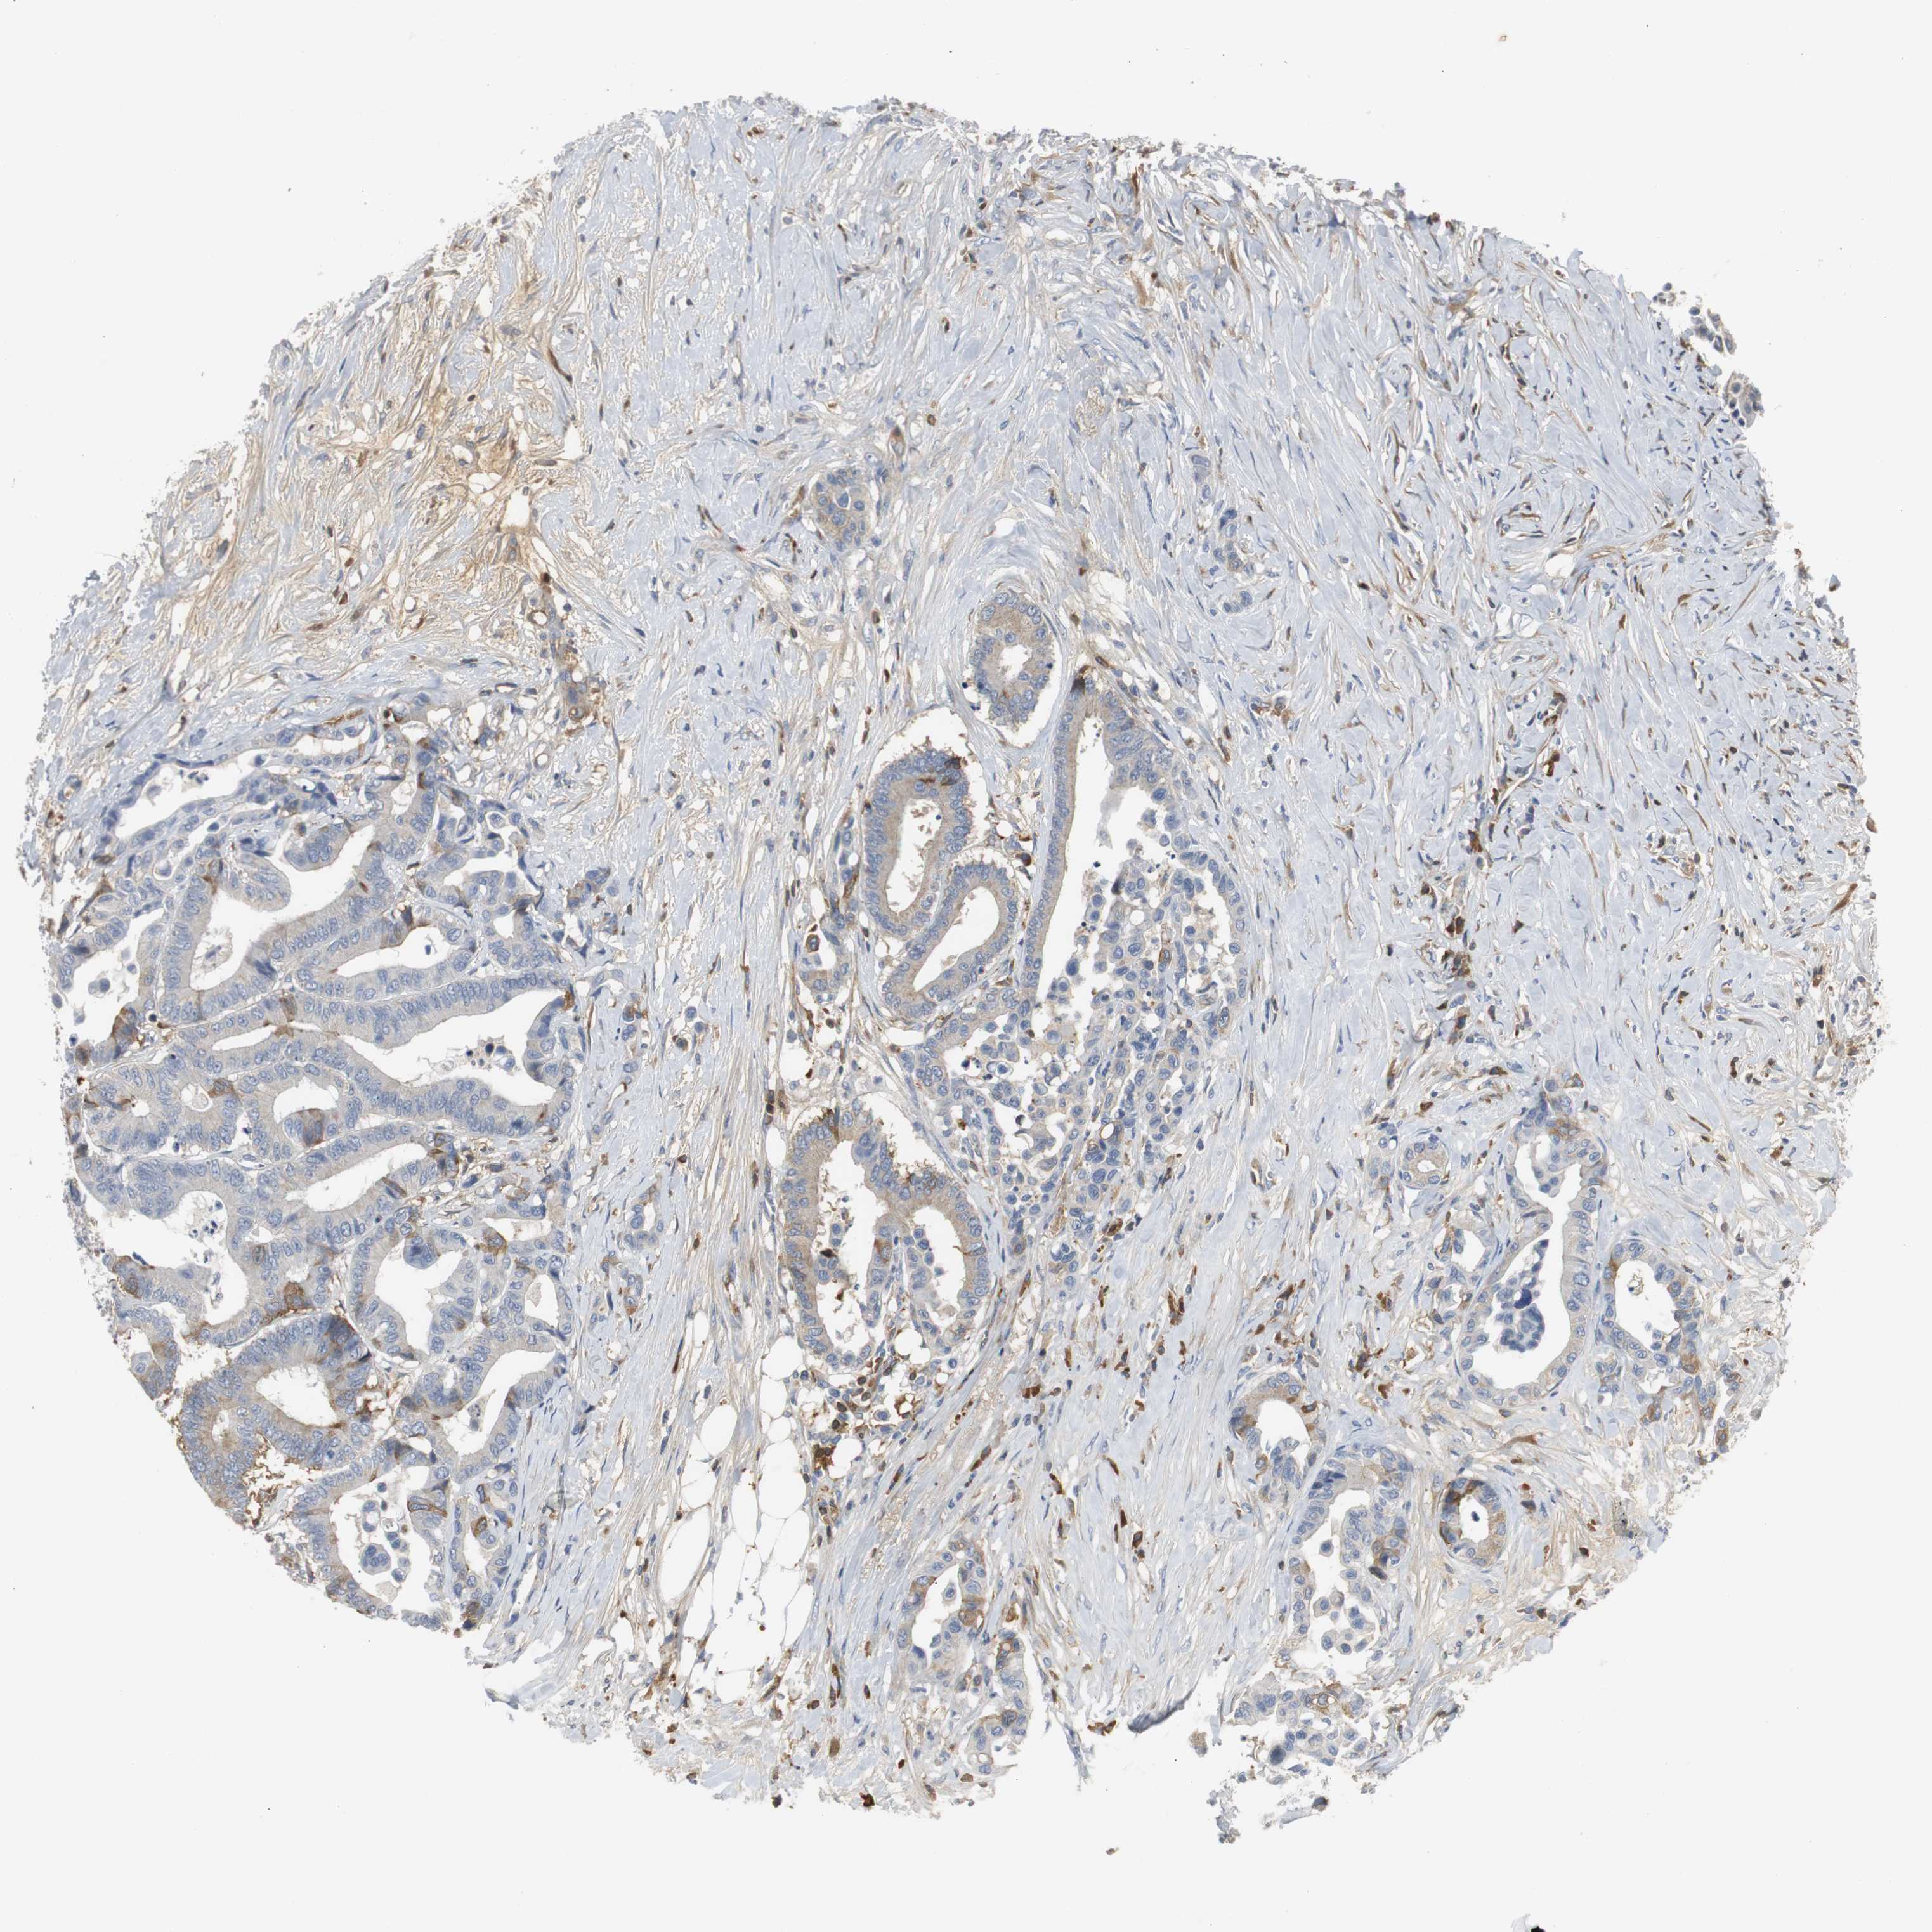

CANCER COLORECTAL CANCER Show tissue menu

Colorectal cancer

Human cancer

Colon adenocarcinoma

Rectum adenocarcinoma